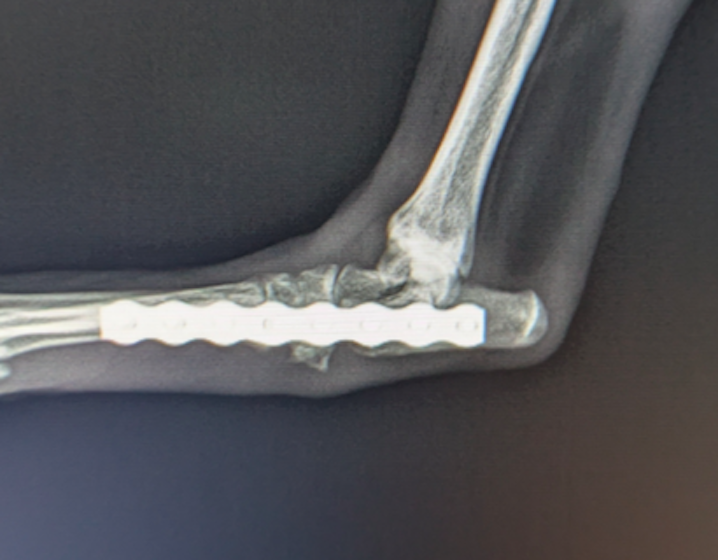

前十字靱帯断裂症例(2025/02/06)

HPの外科の前十字靱帯断裂のページに、犬のTPLO(脛骨高平部水平化骨切り術)手術を行った症例を追加致しました。大腿骨と脛骨を繋ぐ靱帯の一つである前十字靱帯が断裂すると、膝の関節が不安定となり関節炎が進行します。また膝関節内のクッションの役割を果たしている半月板にもダメージが加わり、痛みを生じて正常な歩行が出来なくなります。治療法としては術後の機能回復の早さから、近年ではTPLO法(脛骨の一部を円形に切り、角度を調整し膝関節を安定化させる手術)が多く選択されています。前十字靭帯断裂は中高齢犬によく見られる病気であり、膝蓋骨脱臼に併発することもあります。気になる症状がある場合はお早めにご相談下さい。

獣医師 臼井

症例報告(2024/08/27)

外科の前十字靱帯断裂のページに、犬のTPLO(脛骨高平部水平化骨切り術)手術を行った症例を追加致しました。大腿骨と脛骨を繋ぐ靱帯の一つである前十字靱帯が断裂すると膝の関節が不安定となり関節炎が進行します。また、膝関節においてクッションの役割を果たしている半月板にもダメージが加わり、痛みを生じて正常な歩行が出来なくなります。治療として多くの場合手術が選択されますが、術後の回復の早さなどから近年ではTPLO法(脛骨の一部を切り角度を調整し膝関節を安定化させる手術)が多く選択されています。

獣医師 白石

犬のTPLO(脛骨高平部水平化骨切り術)手術(2024/08/07)

外科の前十字靱帯断裂のページに、犬のTPLO(脛骨高平部水平化骨切り術)手術を行った症例を追加致しました。大腿骨と脛骨を繋ぐ靱帯の一つである前十字靱帯は、断裂すると膝の関節が不安定となり関節炎が進行し、またクッションの役割を果たしている半月板にもダメージが加わることで、痛みを生じて正常な歩行が出来なくなります。治療として多くの場合手術が選択されますが、術後の回復の早さなどから近年ではTPLO法(脛骨の一部を切り角度を調整し膝関節を安定化させる手術)が多く選択されています。